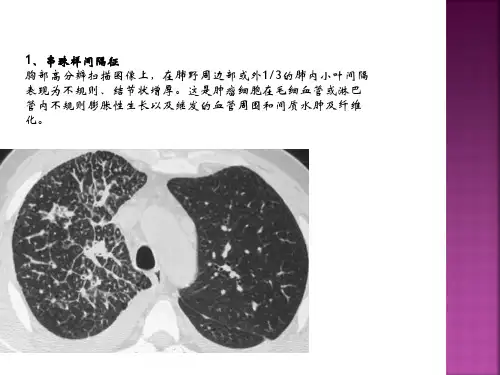

胸部病变基本医学影像征象1、串珠样间隔征胸部高分辨扫描图像上,在肺野周边部或外1/3的肺内小叶间隔表现为不规则、结节状增厚。

这是肿瘤细胞在毛细血管或淋巴管内不规则膨胀性生长以及继发的血管周围和间质水肿及纤维化。

串珠样间隔征的形成,主要是转移瘤细胞或瘤栓经血型或淋巴播散以及逆行性淋巴管转移在肺周边部的毛细血管或淋巴管内,致使转移灶远测血管或淋巴管扩张;转移灶阻塞引起肺间质水肿;病灶在毛细血管和淋巴管周围不规则生长;长期间质水肿继发纤维增生;周边部毛细血管或淋巴管内肿瘤生长并填充其间。

该征主要见于肺转移瘤,其次也见于肺结节病和先天性肺小叶周围纤维化。